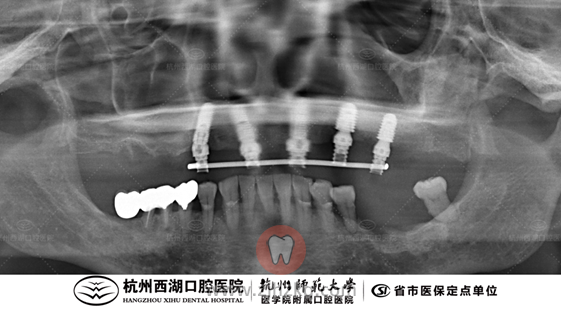

术后CBCT照如下